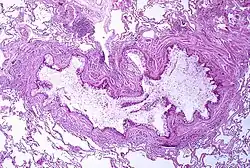

A tissue cross section of the airway showing a stained pink wall and an inside full of white mucous

Ucpání průchodu průdušinky hlenovitým výpotkem, metaplazie pohárkových buněk a epiteliální ztluštění bazální membrány u osoby s astmatem

Astma je výsledkem chronického zánětu dýchacích cest, který má za následek zvýšenou smrštitelnost okolního hladkého svalstva. To spolu s dalšími faktory vede k náhlému zužování dýchacích cest a ke klasickým symptomům sípání. Zužování je typicky vratné s pomocí léčby i bez ní. Příležitostně dochází ke změnám samotné dýchací trubice.[16] Mezi typické změny v dýchacích cestách patří zvýšení počtu eozinofilů a ztluštění retikulárního vaziva. V chronické podobě může hladké svalstvo dýchacích cest nabýt na velikosti a může se zvýšit počet hlenových žláz.K dalším typům buněk zapojených do tohoto procesu patří T-lymfocyty, makrofágy a neutrofily, podílet se na něm mohou ale i další složky imunitního systému, mimo jiné cytokiny, chemokiny, histamin a leukotrieny.[42]